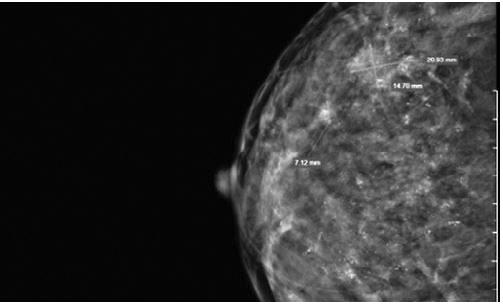

Tại đây, bác sĩ tiến hành thăm khám lâm sàng và chỉ định xét nghiệm cùng các thăm dò chẩn đoán hình ảnh như: siêu âm, chụp X-quang tuyến vú. Kết quả siêu âm vú phát hiện hai khối u tuyến vú phải đều nghi ngờ ác tính. Đặc biệt, hình ảnh chụp X-quang cho thấy hiện tượng vi vôi hóa lan tỏa tuyến vú phải kèm vài hạch vùng hố nách.

Hình ảnh chụp X-quang cho thấy hiện tượng vi vôi hóa lan tỏa tuyến vú phải. |